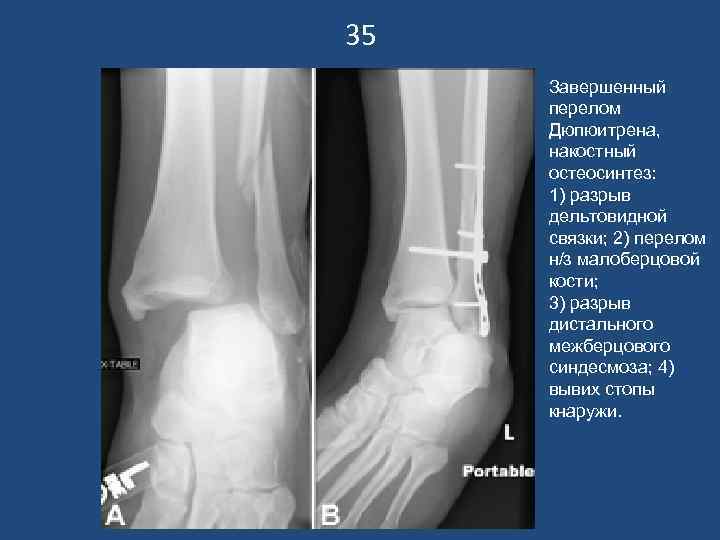

35 Завершенный перелом Дюпюитрена, накостный остеосинтез: 1) разрыв дельтовидной связки; 2) перелом н/з малоберцовой кости; 3) разрыв дистального межберцового синдесмоза; 4) вывих стопы кнаружи.